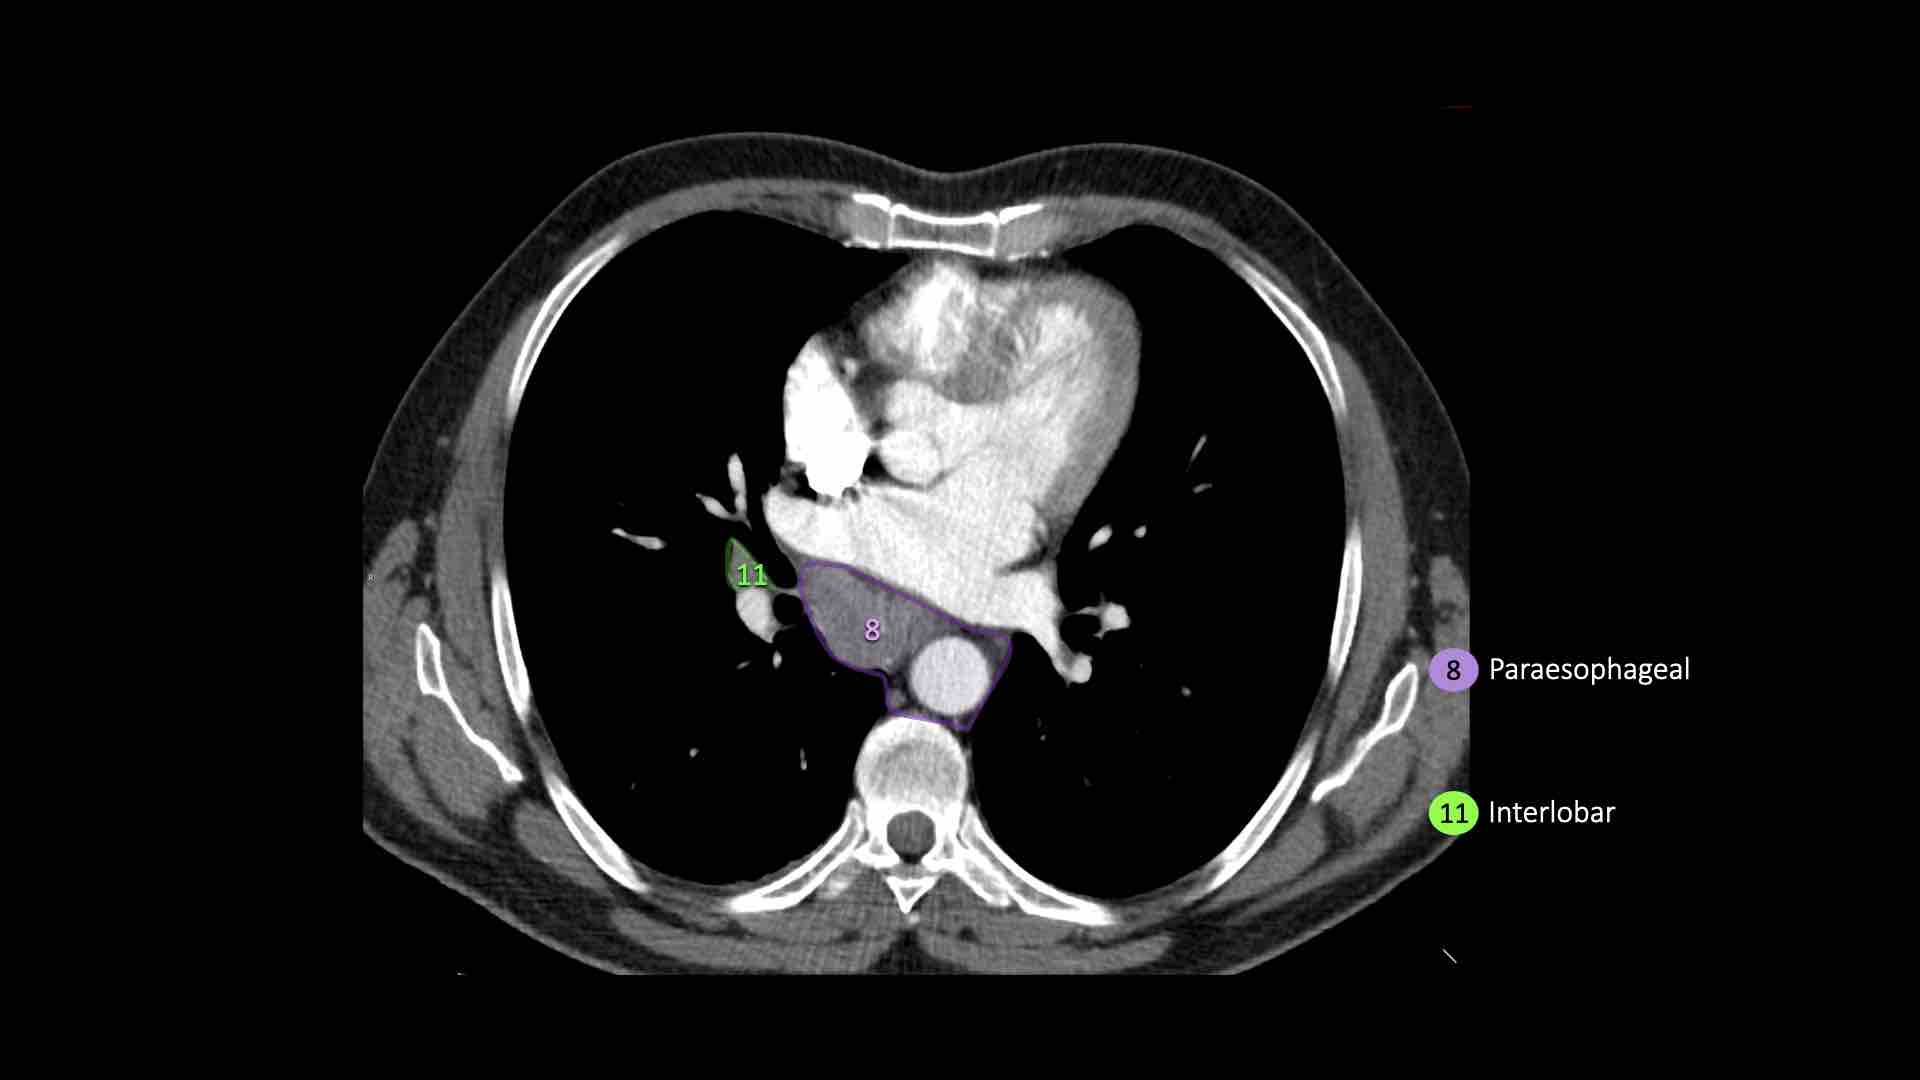

8. Cạnh thực quản

Các hạch nằm dưới carina.

Hạch rốn phổi, thùy phổi và (phân) phân thùy nhóm 10-14

Tất cả các hạch này đều thuộc nhóm N1.

10. Hạch rốn phổi

Bao gồm các hạch tiếp giáp với phế quản gốc và các mạch máu rốn phổi.

Bên phải, trải dài từ bờ dưới tĩnh mạch đơn đến vùng gian thùy.

Bên trái, từ bờ trên động mạch phổi đến vùng gian thùy.

8. Hạch cạnh thực quản

Các hạch này nằm bên dưới các hạch dưới carina và trải dài xuống đến cơ hoành.

Bên trái là hình ảnh dưới mức carina.

Bên phải thực quản là một hạch nhóm 8.

Hạch rốn phổi là các hạch thùy gần, nằm ở phía xa so với nếp gấp màng phổi trung thất và các hạch kề phế quản trung gian bên phải.

Các hạch từ nhóm 10 đến 14 đều là hạch N1, vì chúng không nằm trong trung thất.